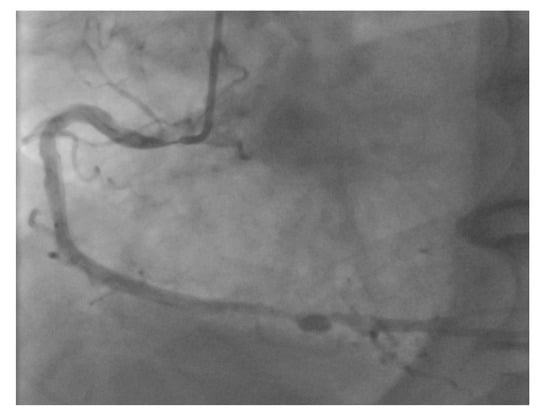

However, an ideal robotic intervention is one where the operator obtains access and performs initial guide placement manually, and is then able to complete the entire intervention from the cockpit without having to re-scrub, even briefly, to perform some portion manually. An example of an excellent case for robotic PCI is a two vessel PCI of the left anterior descending and circumflex arteries, where one guide shape and a single guidewire is used for both vessels, and where significant radiation exposure or a prolonged time in lead are both avoided. Figure 2 shows an example of an ideal robotic PCI case.

Figure 2.

Example of an ideal case for robotic PCI. These images are from a 72 year-old with unstable angina referred to our hospital for intervention. Diagnostic catheterization showed moderate disease in the LAD (A) but with fractional flow reserve of 0.65 and severe disease of the LCX (B) with chronic occlusion of the RCA. The LAD and LCX were both treated successfully robotically with post-stent images shown in (C).